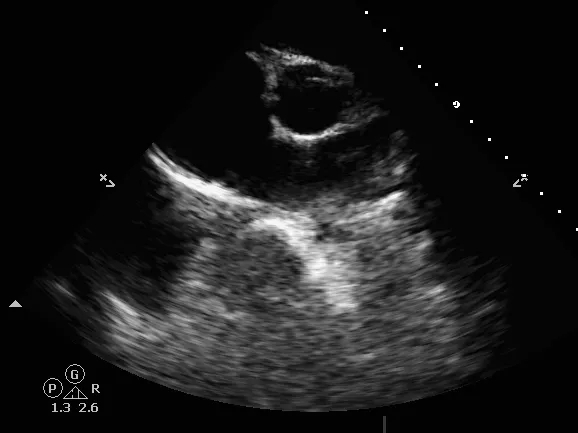

释放后评估

封堵器位置正确、形态良好

彩色多普勒血流成像显示无残余分流存在

封堵成功